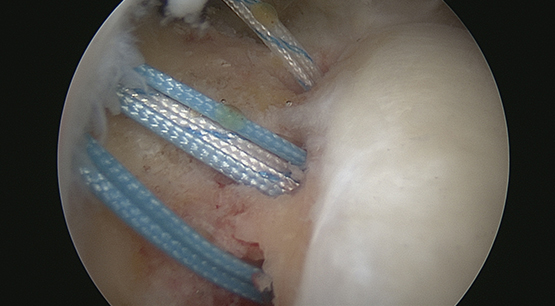

Passage des fils dans la coiffe #1

Passage des fils dans la coiffe #2

Passage des fils dans la coiffe #3